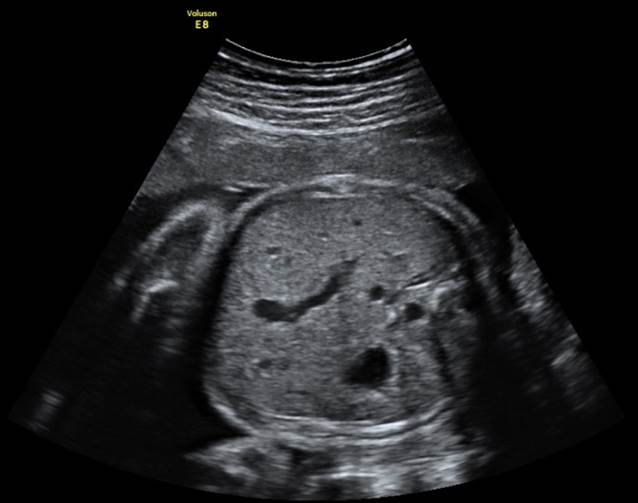

产科_胎儿面部_正中失状面:鼻骨

产科_胎儿面部_胎儿鼻骨三维成像

产科_胎儿面部_冠状面:鼻和唇